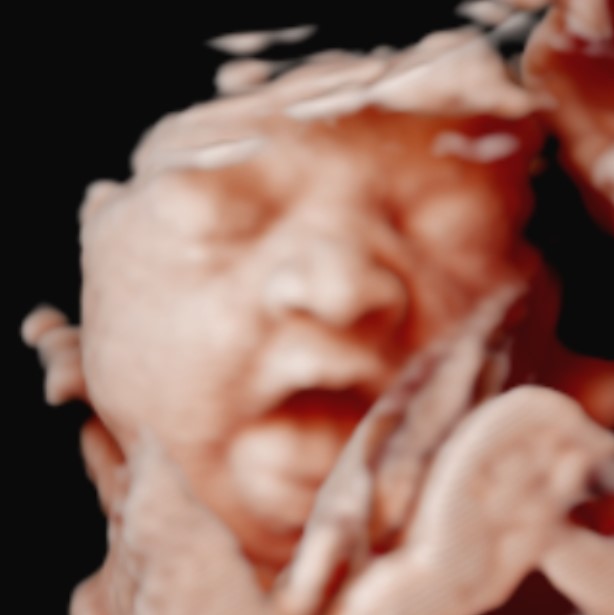

Ultrasound Packages

Gallery